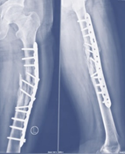

Case-III

62 years, female;

Broken IMN of fracture tibia and fibula (Implant failure) (Figure 11-13).

Figure 11 X-ray broken IM nail after fall.

Figure 12 Post-operative x-ray after Ilizarov operation.

Figure 13 X-ray after union.